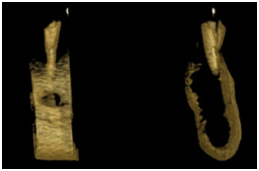

Tomografia computadorizada Reconstruções 3D

Reabsorção radicular adjacente a dentes retidos Reabsorção radicular adjacente a dentes retidos